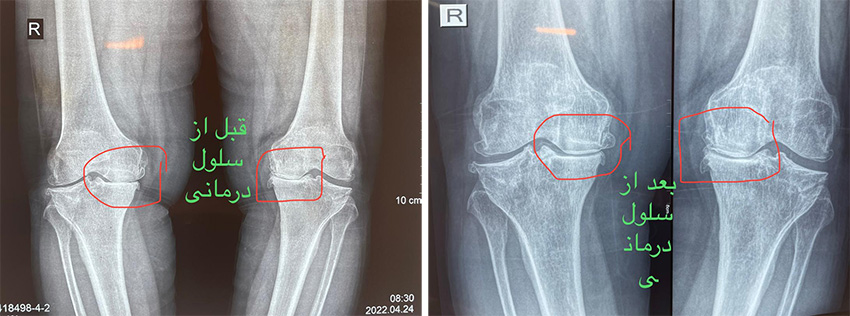

سلول درمانی زانو قبل و بعد